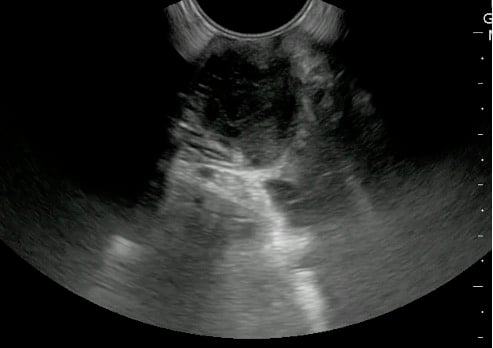

- Endocavitary probe can be used for the evaluation of tonsils.

- A 5.0 to 10.0 MHz curved array intracavitary probe is used to evaluate a suspected PTA for intraoral ultrasound. Alternatively, a high frequency linear array transducer can be used for transcervical approach, especially in children or patients with severe trismus.

- Place probe into the oral cavity over the area in question.

- The peritonsillar area should be systematically scanned in both long and short axes.

- Color Doppler should be used to identify the depth of the carotid artery and surrounding vessels.

- Alternatively, place the linear array transducer inferior and adjacent to the angle of the mandible with rotation of the head to the contralateral side. The tonsil is deep to the submandibular gland, medial to the facial vessels, and lateral to the tongue.

- The ovoid tonsils appear striated with hyperechoic bands and hypoechoic parenchyma, as well as lobulated margins.

- Figure 42 and 43. Normal Tonsil

- Peritonsillar abscess is visualized as a hypoechoic or complex cystic structure

- The carotid artery is seen as an anechoic tubular structure along the posterolateral aspect of the tonsil on ultrasound. Its relationship to the abscess cavity should be determined. Color Doppler can help locate the carotid artery.

- Figure 47 and 48. PTA with color Doppler of carotid artery